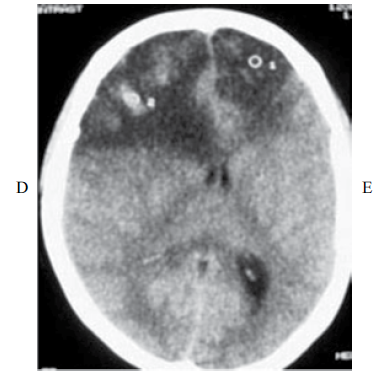

Paciente com 22 anos de idade foi admitida a serviço de emergência devido a comprometimento do nível de consciência há um dia. Ao exame físico, estava febril (39 °C), pressão arterial 70x50 mmHg, comatosa, sem resposta aos estímulos nociceptivos, pupila direita midriática. A família refere que a paciente se queixava de cefaleia há três dias. Como antecedentes, a paciente estava em tratamento com azatioprina 75 mg/dia e predinisona 20 mg/dia, devido a ulcerocolite O hemograma mostra 12 000 leucócitos/mm 3 (82% polimorfonucleares, 18% linfócitos), hemoglobina de 9 g/dL, e potássio sérico de 2.8 mEq/L. A tomografia de crânio é mostrada a seguir:

enunciado 823168-1